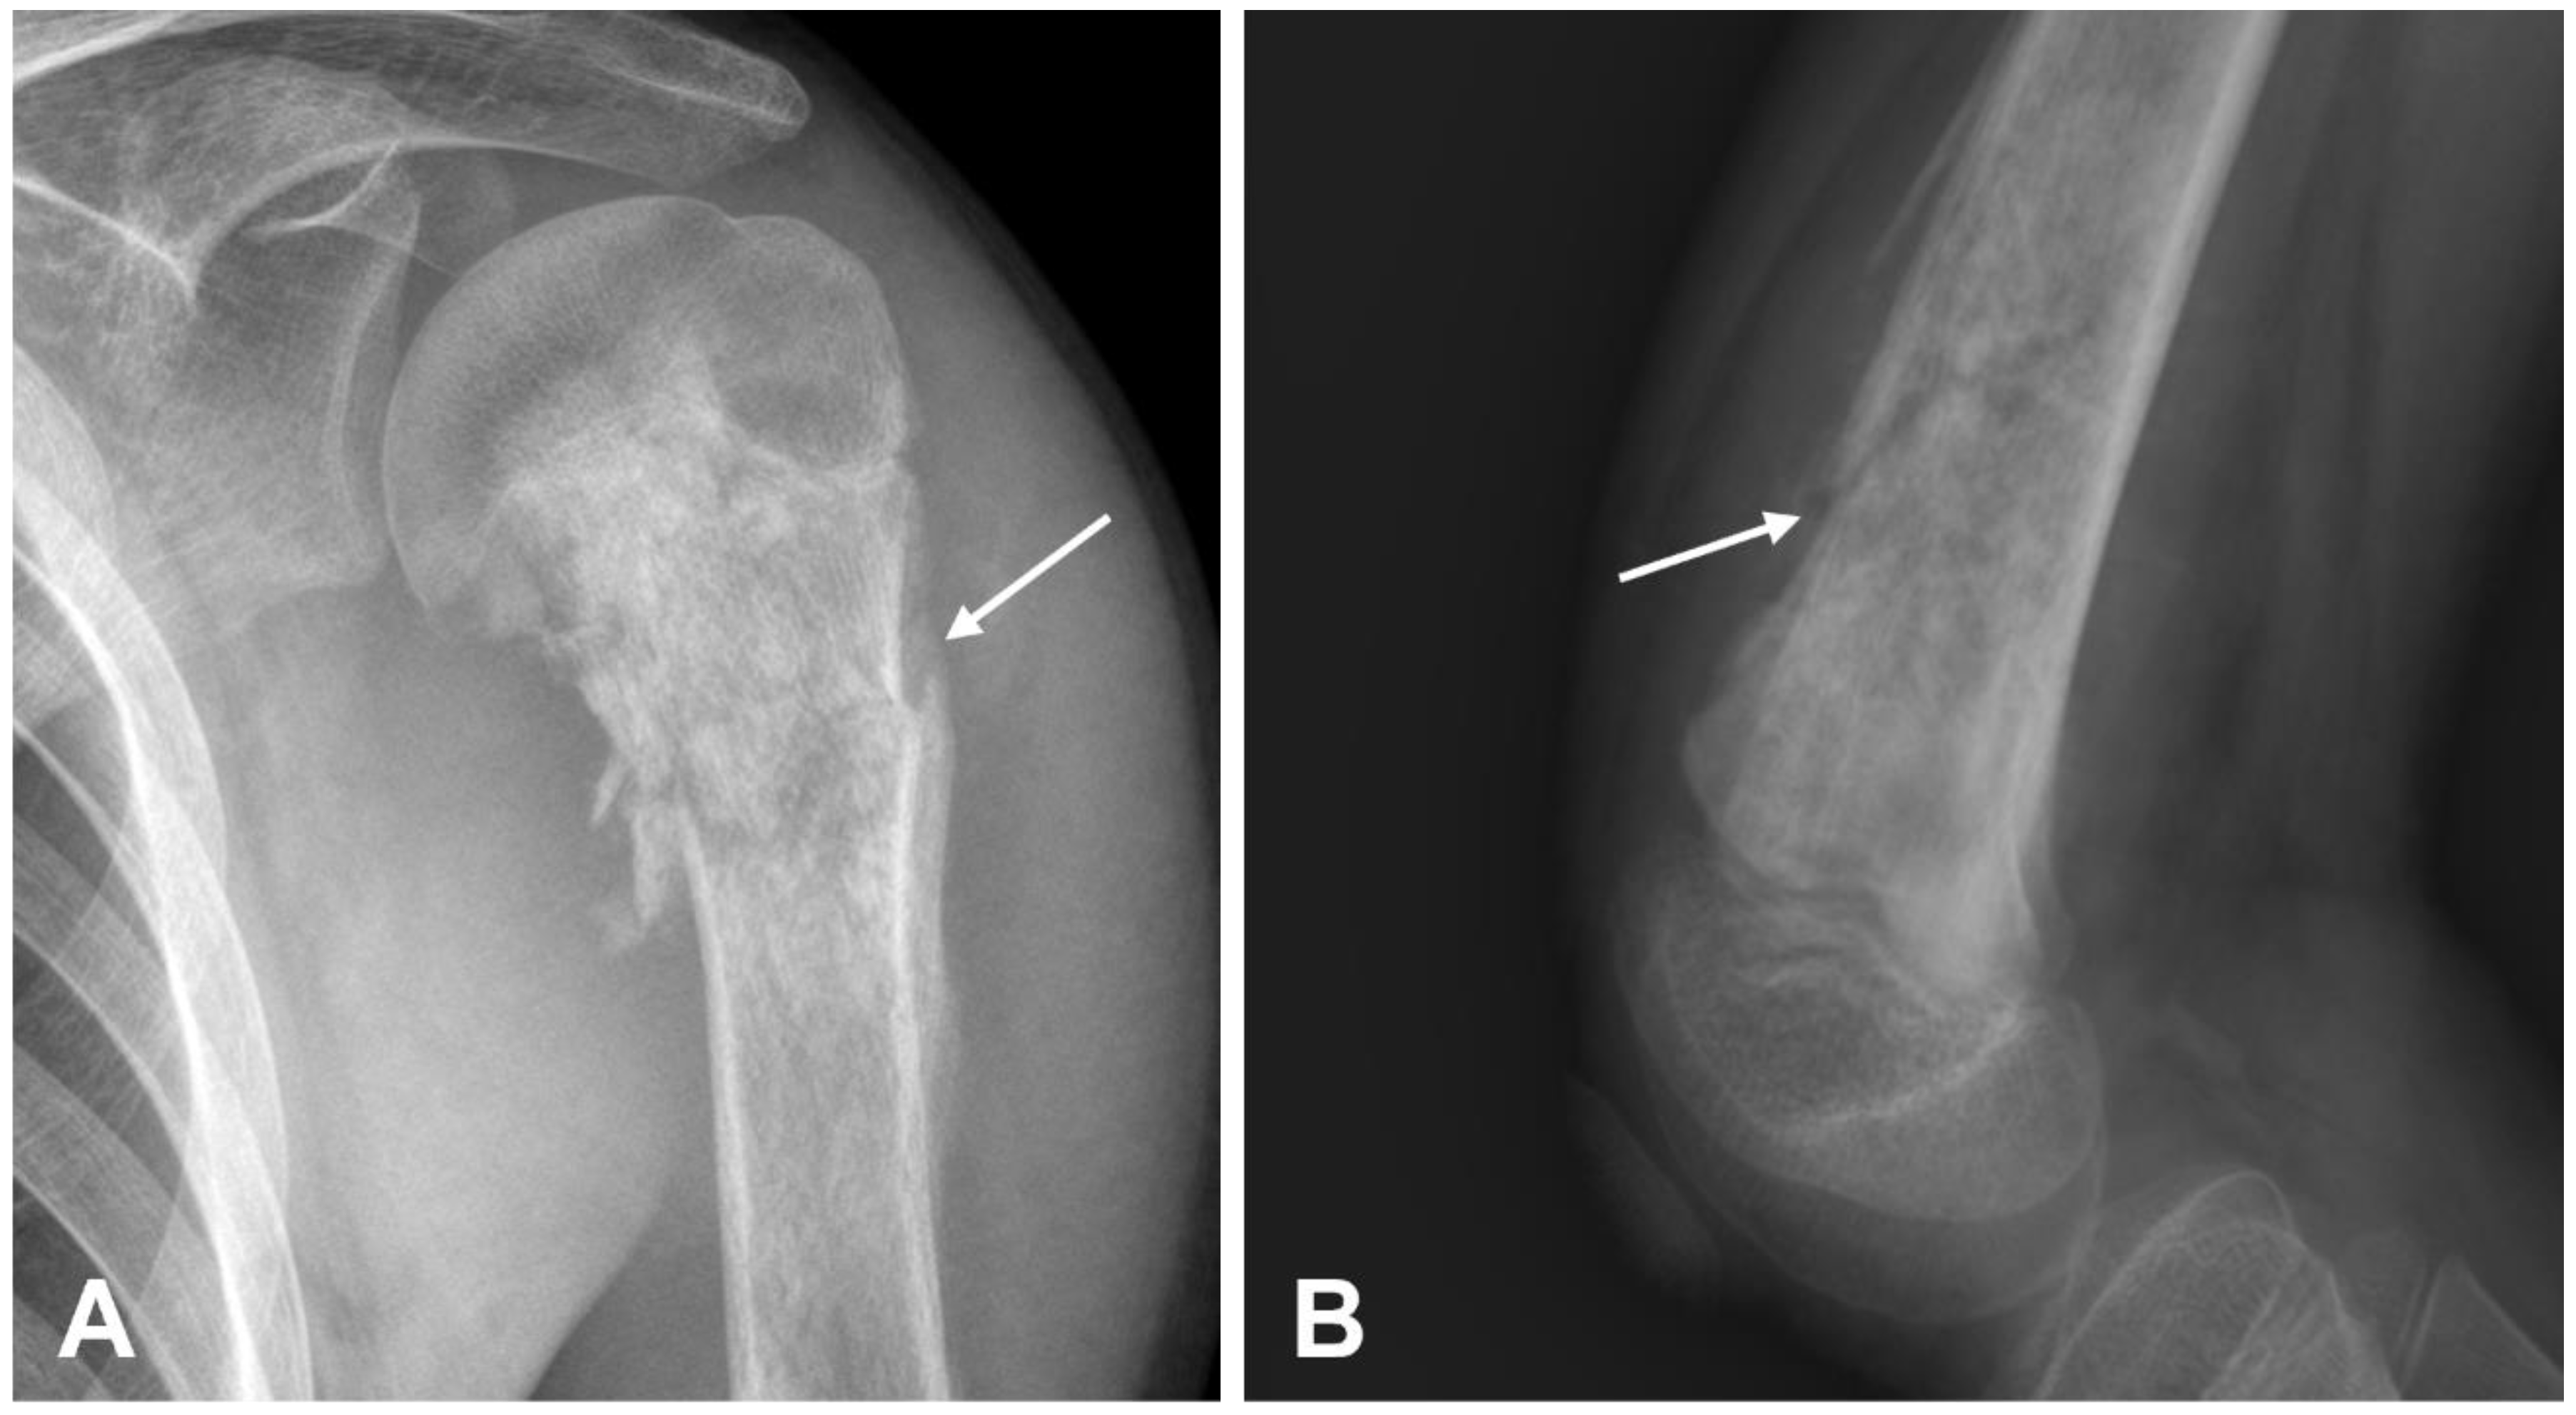

3.1.1. Conventional Osteosarcoma

- Murphey, M.D.; Robbin, M.R.; McRae, G.A.; Flemming, D.J.; Temple, H.T.; Kransdorf, M.J. The Many Faces of Osteosarcoma. RadioGraphics 1997, 17, 1205–1231. [Google Scholar] [CrossRef] [PubMed]